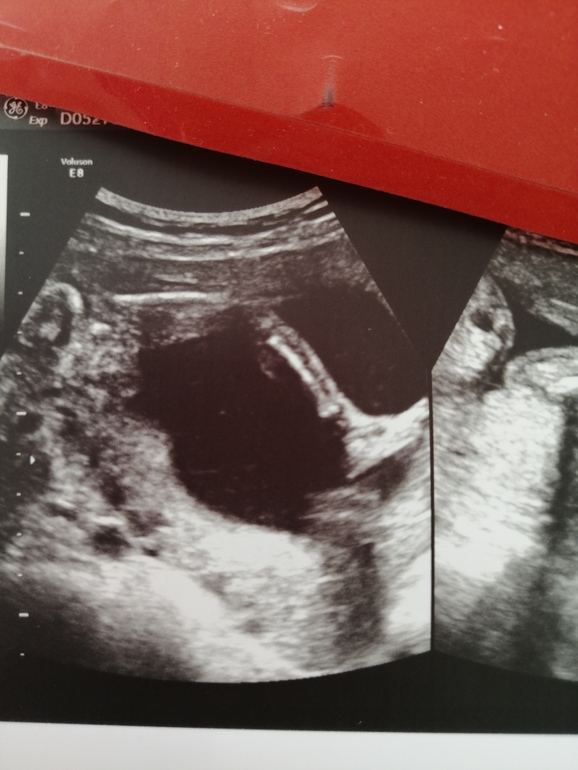

А пока 20 неделек, по мес побольше, но в этот раз мы с самого начала немного отстаём, поэтому считаю по узи.

И покажу вам ножку своей сладкой зефирки, которыми она пляшет на шейке, как сказала узистка, балерина моя🥰👸🤗